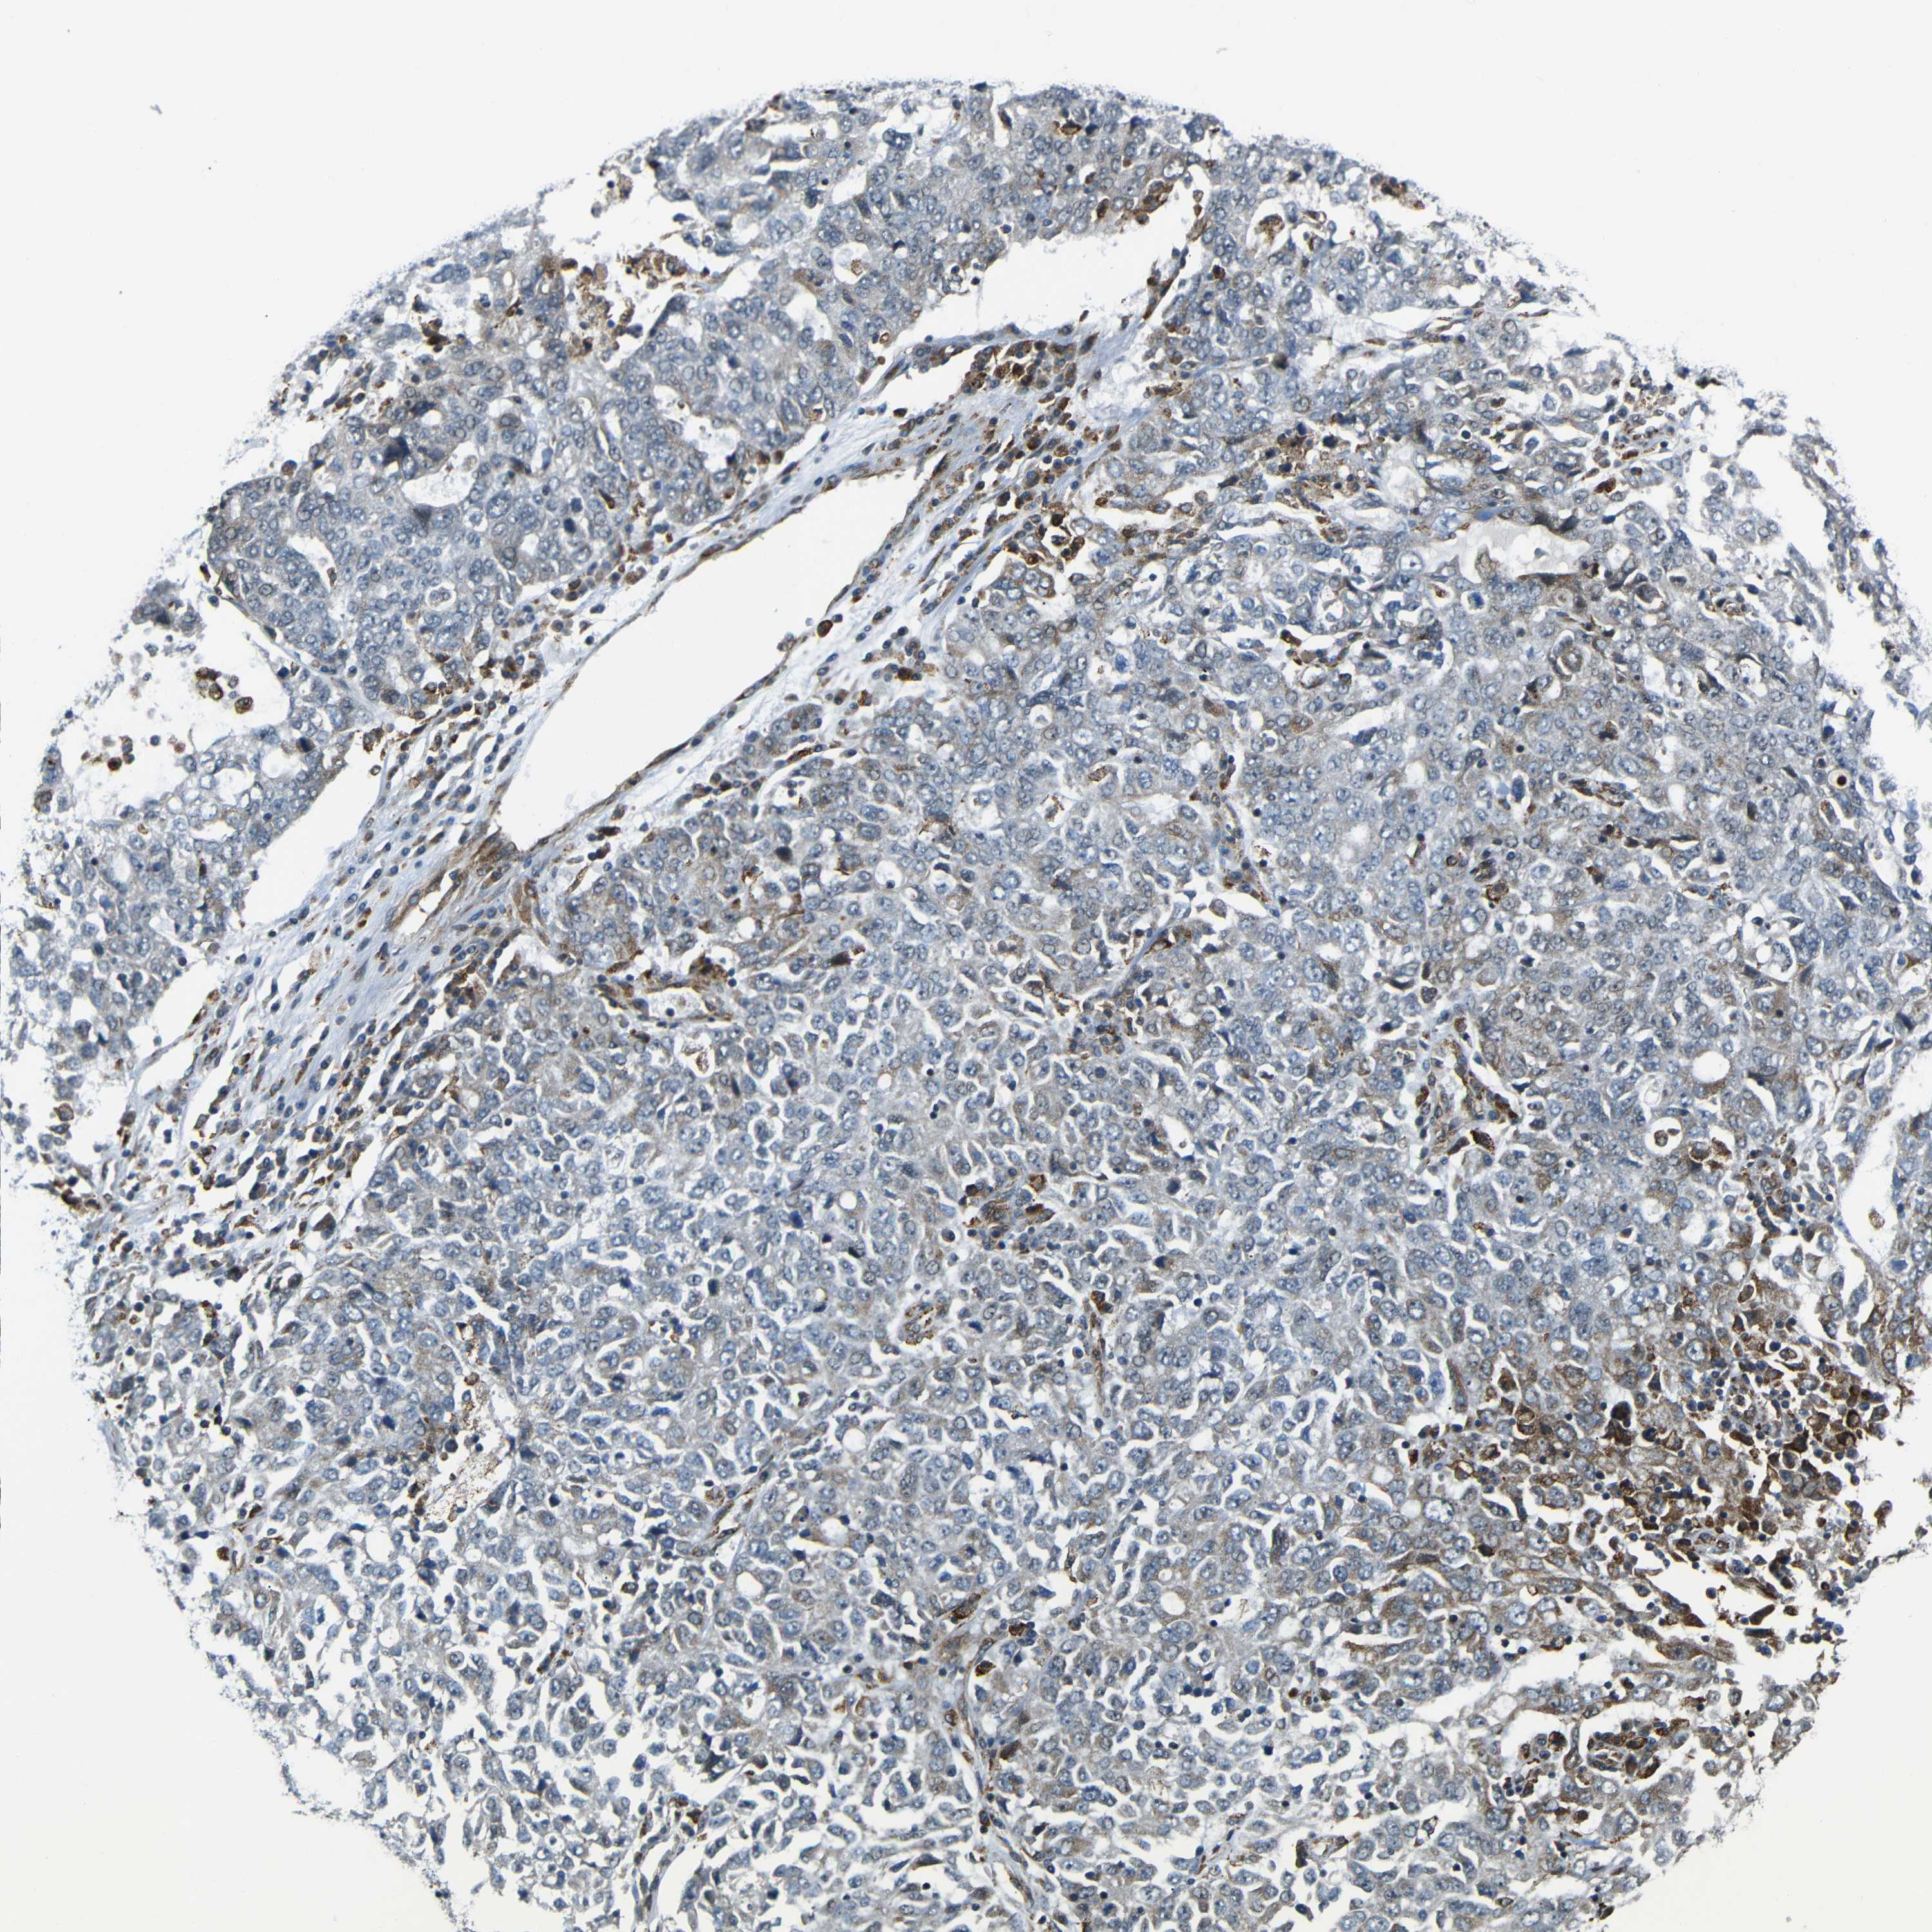

OVARIAN CANCER - Protein expressioni

A mouse-over function shows sample information and annotation data. Click on an image to view it in a full screen mode. Samples can be filtered based on level of antibody staining by selecting one or several of the following categories: high, medium, low and not detected. The assay and annotation is described here.

Note that samples used for immunohistochemistry by the Human Protein Atlas do not correspond to samples in the TCGA dataset.

Antibody stainingi

Antibody staining in the annotated cell types in the current human tissue is reported as not detected, low, medium, or high, based on conventional immunohistochemistry profiling in selected tissues. This score is based on the combination of the staining intensity and fraction of stained cells.

Each image is clickable and will lead to virtual microscopy that enables deeper exploration of all samples and also displays staining intensity scores, fraction scores and subcellular localization as well as patient and tissue information for each sample.

Antibody HPA013328

Staining

High

Medium

Low

Not detected

Intensity

Strong

Moderate

Weak

Negative

Quantity

>75%

75%-25%

<25%

None

Location

Nuclear

Cytoplasmic/membranous

Cytoplasmic/membranous,nuclear

Cystadenocarcinoma, serous, NOS

Carcinoma, endometroid

Cystadenocarcinoma, mucinous, NOS

Carcinoma, NOS